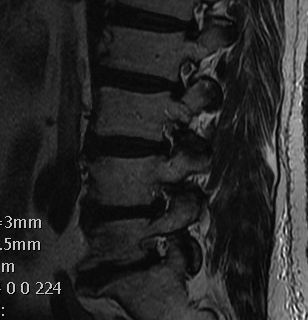

MRI

T2 Sagittal - myelogram

T1 Axial - see nerve root against white fat

Wiltse Classification

1. Bulge

- annulus diffusely extends beyond the plane of the disc space

- annulus intact / nil focal protrusion

2. Protrusion

- focal bulging within margin of annulus

- diameter of base is greater than diameter of tissue displaced beyond disc space

3. Extrusion

- under PLL

- mass of discal tissue of greater diameter than the aperature through which it has passed

4. Sequestration

- free disc in canal

- fragment with no continuity with tissue in disc of origin